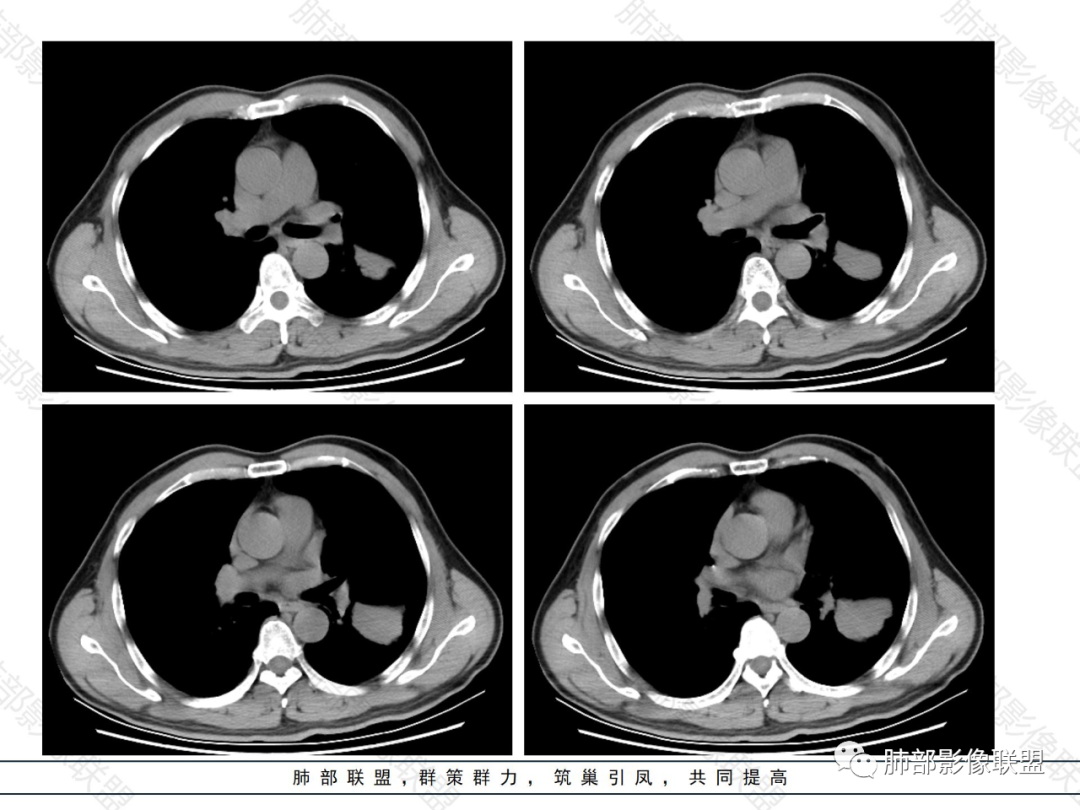

病变分布特点,胸膜下,叶间胸膜下为主,呈大小不等结节级团块影,部分病灶内见支气管影,病灶收缩不明显,从分布及慢性发病看,隐球和淋巴瘤都可,补充增强,病灶内见血管穿行,强化不明显,支持淋巴瘤

老年男性,两肺多发结节肿块,胸膜下分布为主,部分支气管进入闭塞,增强扫描有强化,血管穿行无破坏,边缘尚光滑,周围无晕,病灶整体膨隆为主,半年病程,症状逍遥,首先考虑淋巴瘤

棉花糖:双肺多大小不等结节,边缘清楚,无毛刺,浅分叶,胸膜下分布为主,内可见支气管穿行,增强后中等程度强化,病灶内血管走行自然,考虑淋巴瘤,鉴别GPA

均匀强化

内部血管走形自然,稍纤细

这里似乎稍增粗

4.血管造影征:肿瘤组织浸润引起间质增厚、肺泡壁破坏、肺泡腔充填,而周围充盈血管走行自然,未受肿瘤侵犯。血管造影征